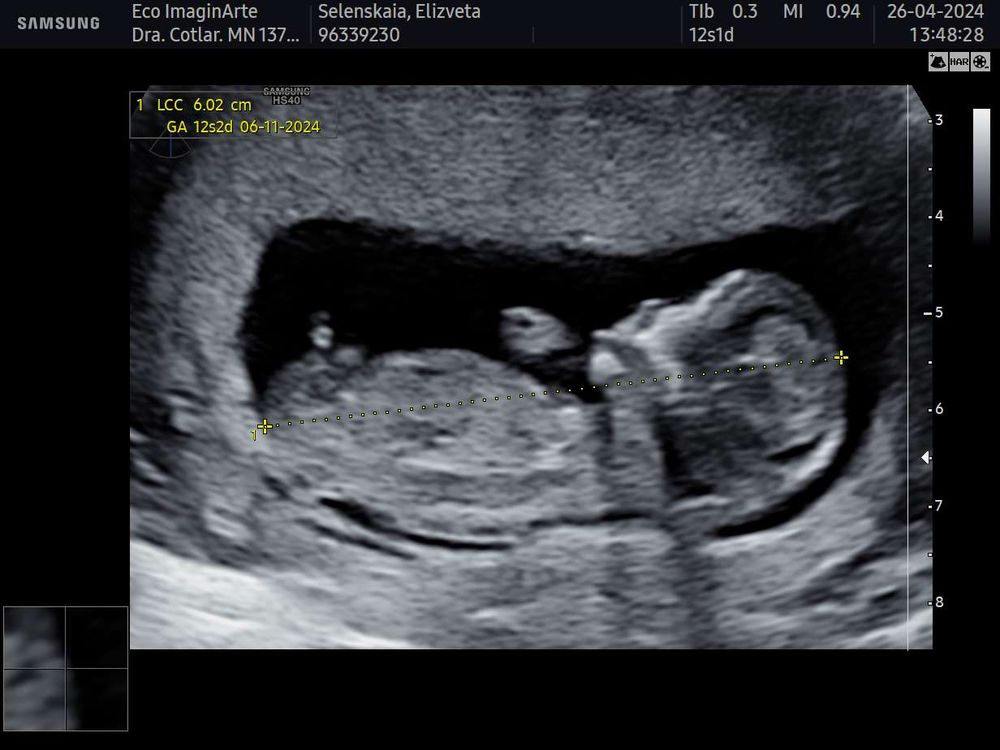

Пол в 15 недель 2 дня, мальчик?

И видно ли тут ?)